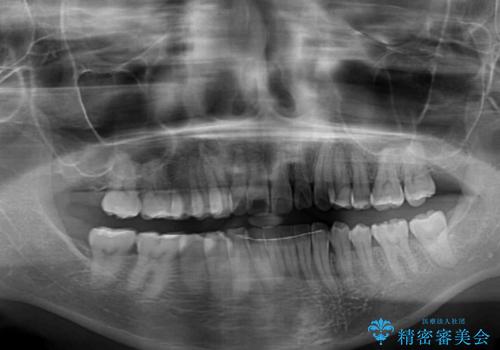

カリエール・ディスタライザーを用いたことで上顎前歯の突出感はスムーズに解消され、歯列不正は1年半ほどでほぼ改善することができました。

しかし、その後インビザライン特有の奥歯がうまく噛めないという問題が長引き、改善に1年近い期間を要することとなりました。